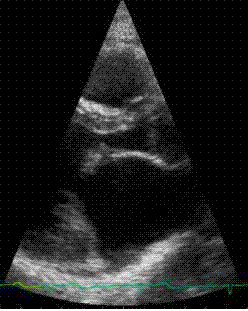

Here

is an animation clip of the acutal echocardiogram, showing

the prolapsing valve. The animation is paused at the prolapse

so that it can be clearly seen.